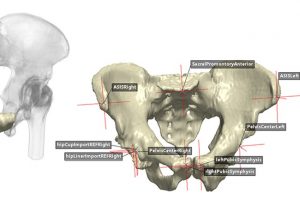

- 人工智能自动分割工具:前庭神经鞘瘤的 3D 体积分析 2025年6月20日